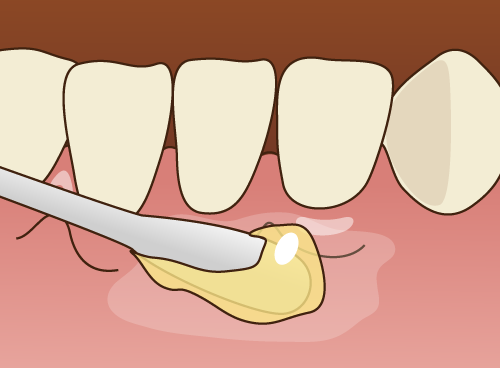

・表面麻酔で注射の痛みを軽減

親知らずの抜歯の際、多くの患者さんが不安に感じるのは、麻酔の注射です。当院では、麻酔注射の前に表面麻酔を行い、注射の痛みを極力抑えるよう努めています。表面麻酔とは、麻酔の薬を歯ぐきに塗布して感覚を鈍くするもので、針を刺す瞬間の痛みを感じにくくする効果があります。この表面麻酔を使用することで、患者さんに少しでも快適な治療体験を提供します。

親知らずの抜歯の際、多くの患者さんが不安に感じるのは、麻酔の注射です。当院では、麻酔注射の前に表面麻酔を行い、注射の痛みを極力抑えるよう努めています。表面麻酔とは、麻酔の薬を歯ぐきに塗布して感覚を鈍くするもので、針を刺す瞬間の痛みを感じにくくする効果があります。この表面麻酔を使用することで、患者さんに少しでも快適な治療体験を提供します。・極細注射針で針の痛みを軽減